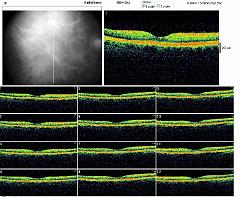

OCT OD

OCT OG